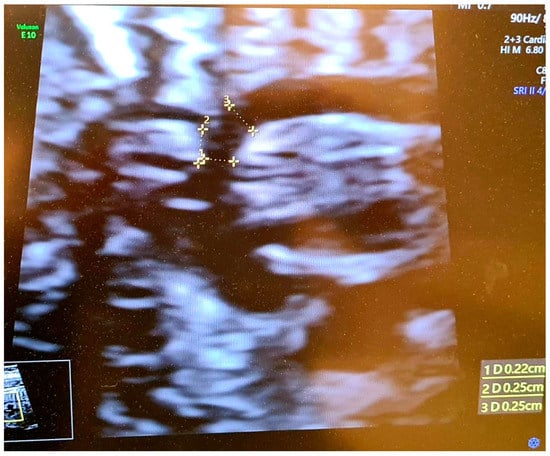

To ensure accuracy in the measurement process, we have provided a visual representation of the correct method of measurement, which can be found in Figure 1 and Figure 2.

Figure 2. Ultrasound view: Correct visualization of the aortic arch at 23.5 week of pregnancy—with visible brachiocephalic trunk. The dimension from carotid distance to subclavian (2 D) = 2.5 mm, transverse aortic dimension (1 D) = 2.2 mm, calculated CSAi = 0.88. Aortic isthmus (3 D) 2.5 mm, z-score = −0.58.